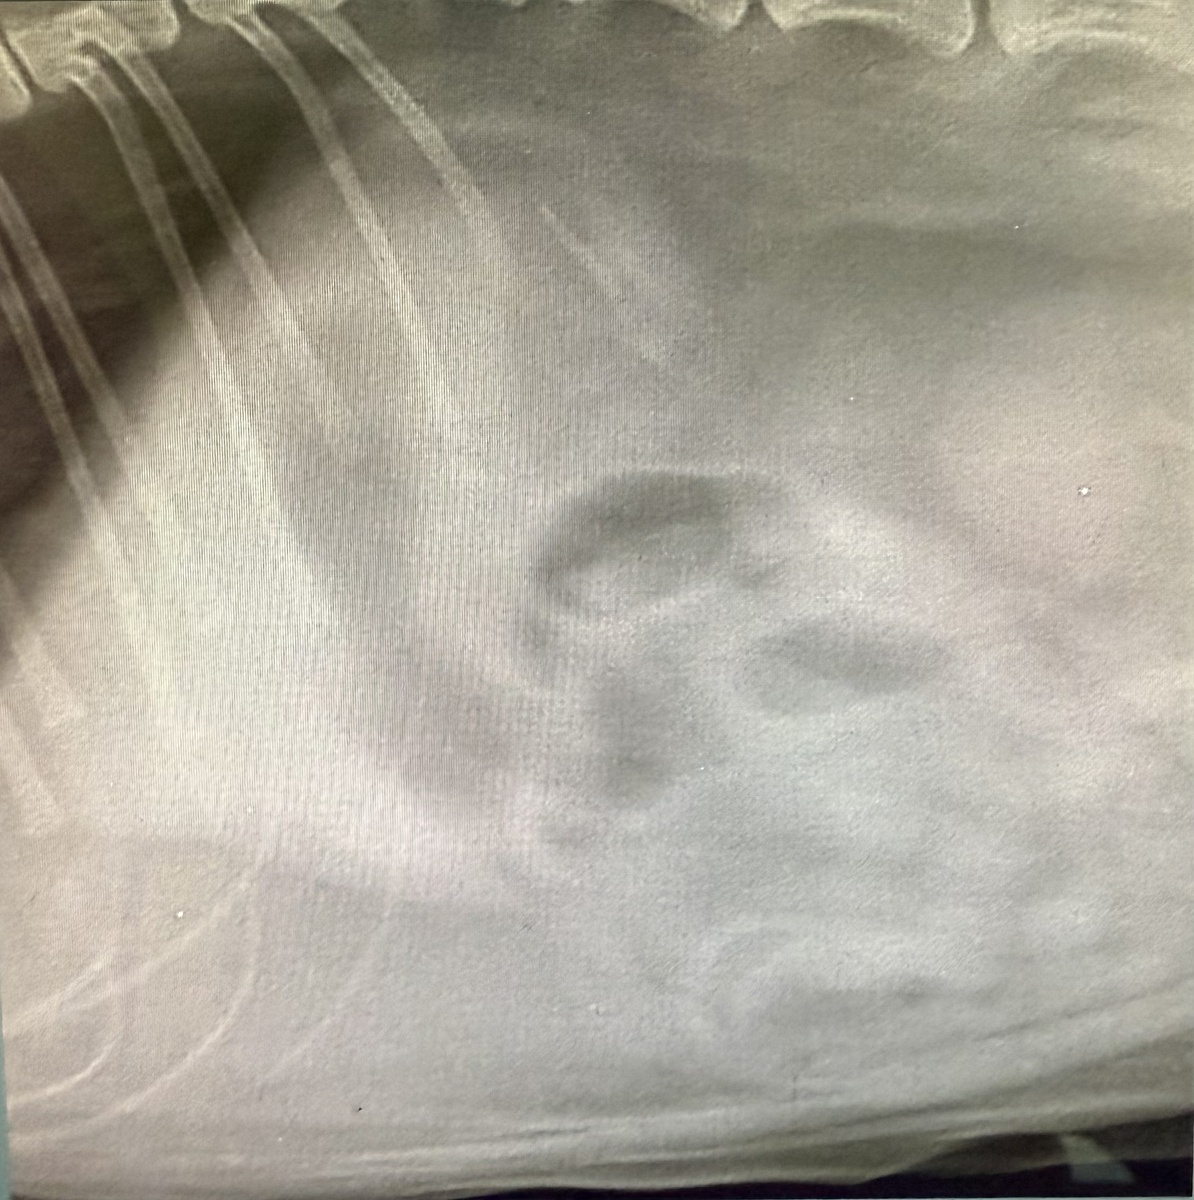

Мы сразу же приступили к обследованию. Диагноз – инородное тело в тонком отделе кишечника. Требовалась экстренная операция. И вот что мы обнаружили внутри – кусочек обычного резинового коврика! Кот, видимо, от скуки, разгрыз его и проглотил.

ИТ на рентгене.